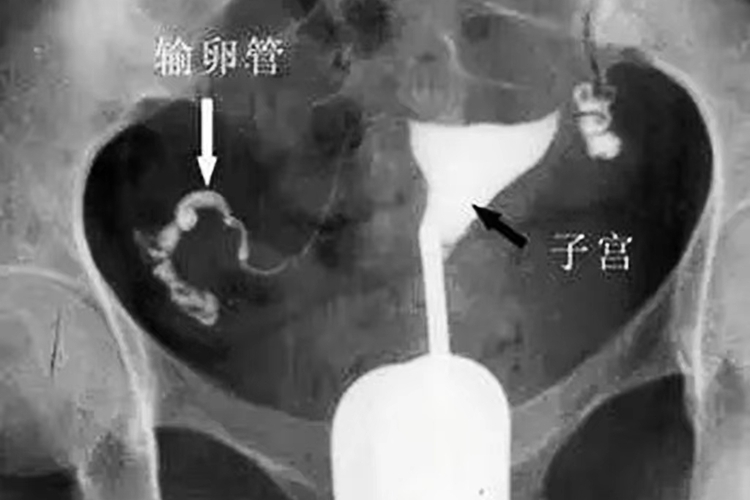

正常子宫、输卵管进行传统的子宫输卵管造影时,可见宫腔呈倒三角形,双侧输卵管显影,形态柔软,24小时后摄片见盆腔内散在造影剂分布,超声下子宫输卵管造影时可实时监控,见造影剂充盈宫腔,并从双侧输卵管流出并包绕同侧卵巢。

输卵管结核显示输卵管形态不规则、僵直或呈串珠状,有时可见钙化点。输卵管积水可见输卵管远端呈气囊状扩张。输卵管发育异常时可显示输卵管过长或过短、缺失、异常扩张、憩室等。传统的子宫输卵管造影时24小时后盆腔X线摄片未见盆腔内散在造影剂,说明输卵管不通畅,而超声下子宫输卵管造影时未见造影剂从双侧输卵管流出,盆腔内未见造影剂,则提示输卵管不通畅。